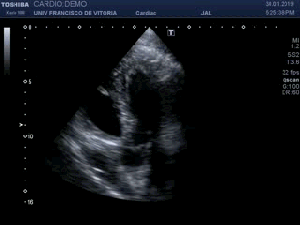

142. Ecocardiografía.Plano Apical 4 cámaras